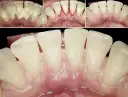

Zapalenie dziąseł spowodowane płytką nazębną i kamieniem

To zdecydowanie najczęstsza przyczyna obrzęku dziąseł. Gdy płytka nazębna, czyli lepka warstwa bakterii, nie jest regularnie usuwana, twardnieje, tworząc kamień nazębny. Bakterie te podrażniają dziąsła, prowadząc do stanu zapalnego, zwanego gingivitis. Typowe objawy to zaczerwienienie, obrzęk, tkliwość oraz krwawienie dziąseł, zwłaszcza podczas szczotkowania. Według danych Mayo Clinic, zapalenie dziąseł to najczęstsza przyczyna krwawienia i obrzęku dziąseł.Uwięziony pokarm, uraz szczoteczką, nitką lub wykałaczką

Objawy typowe dla gingivitis

- Dziąsło jest zaczerwienione i lekko spuchnięte.

- Dziąsło jest tkliwe, ale ból jest zazwyczaj łagodny lub umiarkowany.

- Może występować krwawienie dziąseł podczas szczotkowania lub nitkowania.

- Nie ma ropy ani silnego, pulsującego bólu.

- Brak objawów ogólnych, takich jak gorączka czy złe samopoczucie.